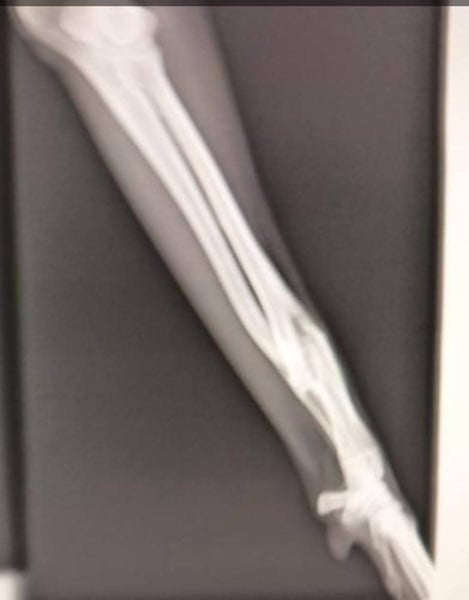

Wahrscheinlich wurde sie aufgrund eines verheilten Bruchs im Vorderbein ausgesetzt. Diese leichte Verletzung hindert sie nicht daran, ein normales Leben zu führen und eine Operation ist nicht notwendig.